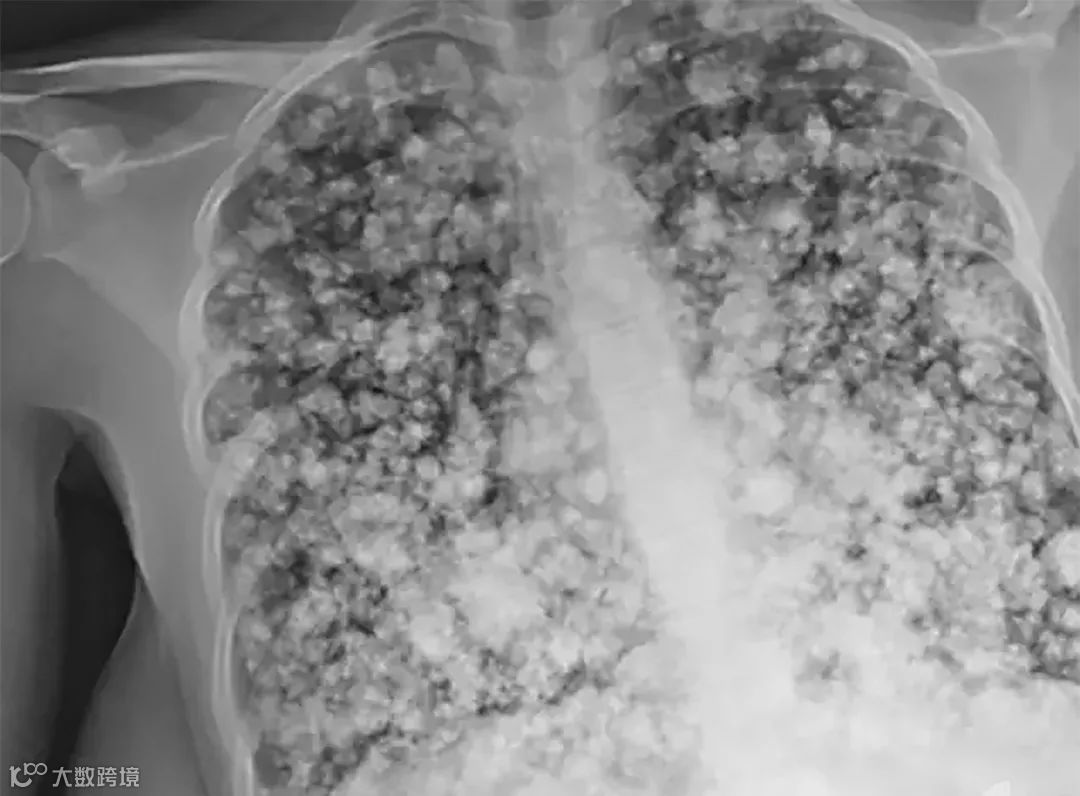

非吸烟者vs吸烟者的肺▼